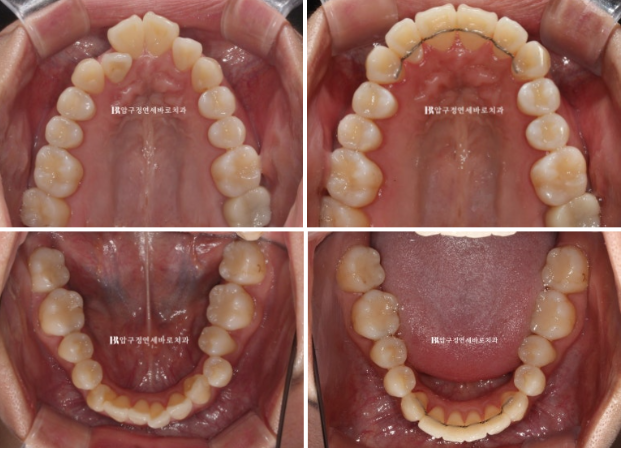

입천장에 위치하는 측절치

24.02

위에는 안보이는 설측 2D장치를 아랫니는 작은어금니 덧니까지 배열하기 위해 MTA 장치를 추천드렸습니다.

24.07 2D 설측 장치 교정

설측장치인 2D 부분교정용 장치 모습입니다.

뒤로 붙이니 교정기간 내내 보이지 않습니다.

덧니 작은어금니를 제 위치로 넣기 위해 아래는 앞니 포함 9개 치아에 MTA 장치를 붙이고 배열했습니다.

2달 간 마무리 교정 후 치료시작 6개월 만에 치료를 마무리 했습니다.

정확히 맞아 떨어지는 중심선

24.02~24.08

작은 어금니까지 배열을 마쳤습니다.